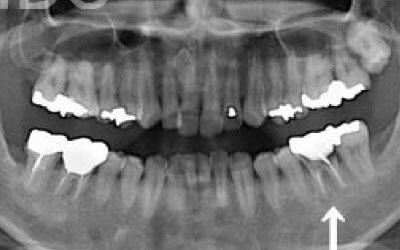

CTでは、骨や歯の状態を3Dで確認でき、正確な距離の測定も行えます。

骨の厚さや傾き、神経の位置などを事前にしっかりと測定することで、安全にインプラントを行うことができます。

1人の歯科医師の視点でなく、複数のドクターでCTの診断や計画を立てています。

ただし、事前にCTで三次元的に神経との距離を測り、治療計画を慎重に立てれば、心配することはありません。

また、当院では過剰に削らないようにするためのストッパーも使用しています。